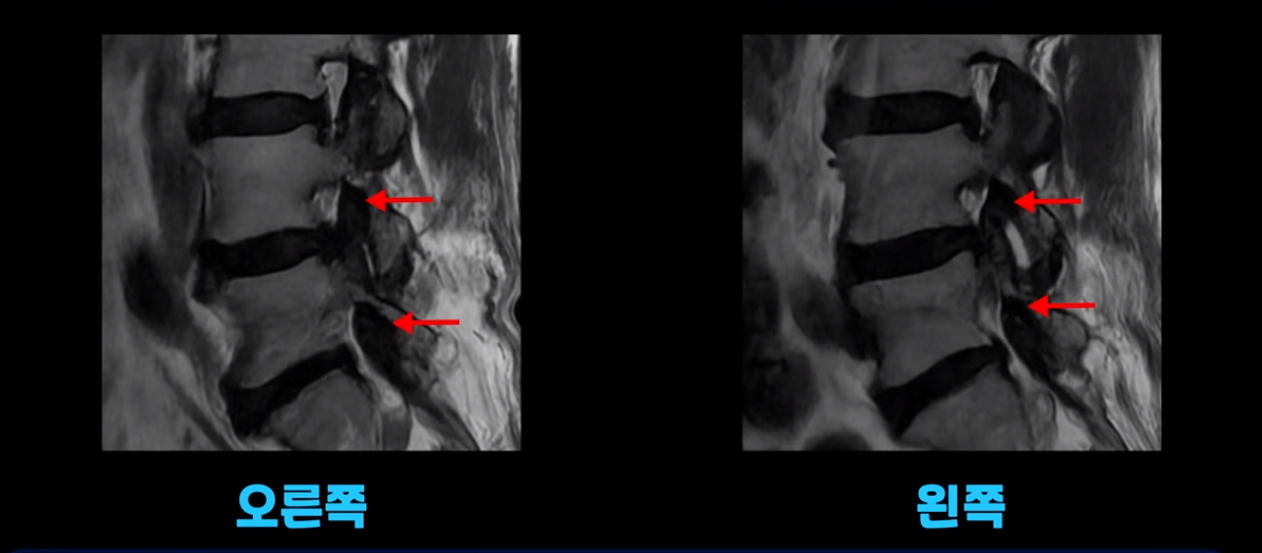

오른쪽 왼쪽 신경 가지가 나가는 추간공도 좁아져는 있지만 아주 심하지는 않습니다.

이 환자분의 가장 큰 문제는 허리를 펴는 근육인 척추기립근이 상당 부분 지방으로 변해서 하얗게 보이고 기립근의 크기도 많이 작아져 있습니다.

이 기립근은 허리를 펴주는 근육인데 이렇게 문제가 생기면 허리가 구부러집니다. 또한 이분의 근육 상태를 알 수 있는 근감소증 검사에서 중증 근감소증 진단이 나왔습니다.

평균적인 동년배들에 비해 근육량이 많이 줄어든 겁니다. 이렇게 근육량도 많이 줄어들고 또 남아있는 근육이 지방으로 변한 상태에서 그나마 남아있는 근육들마저도 뭉치고 굳어서 제 기능을 못 하면 허리가 구부러지고 걸을 때 다리가 힘들고 아플 수밖에 없습니다. 그런데 근육 치료와 이런 근육의 문제를 MRI를 찍어보고 협착이 조금이라도 보이면 협착증으로 진단하고 주사 놓고 안 되면 수술까지 하는 경우들이 있습니다.